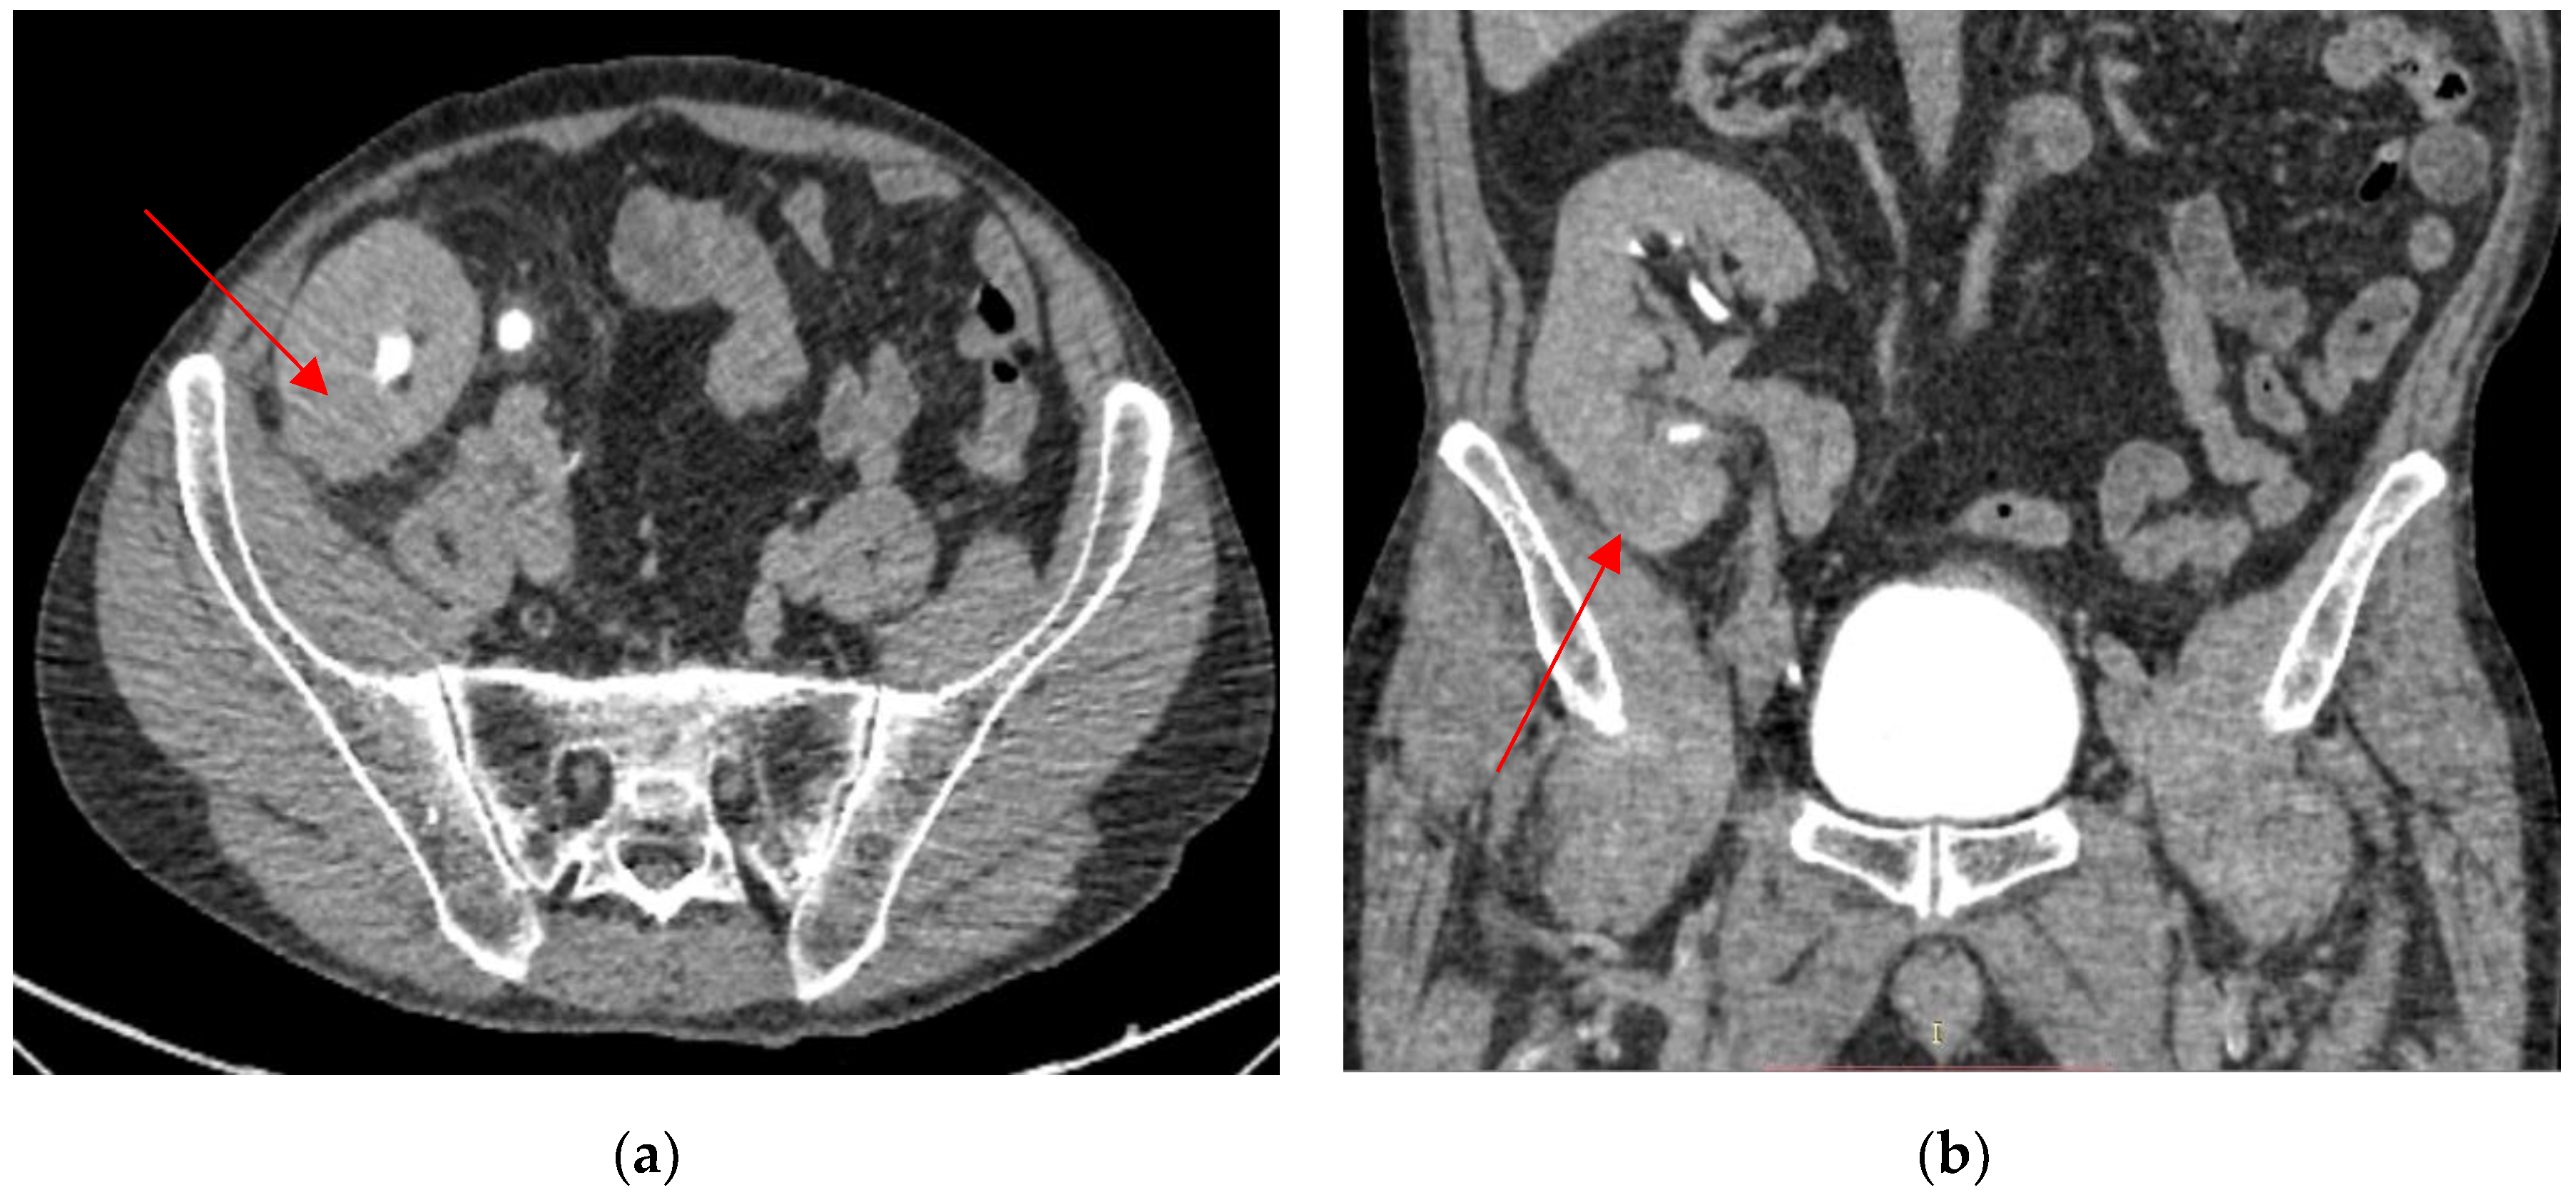

2. Case Presentation